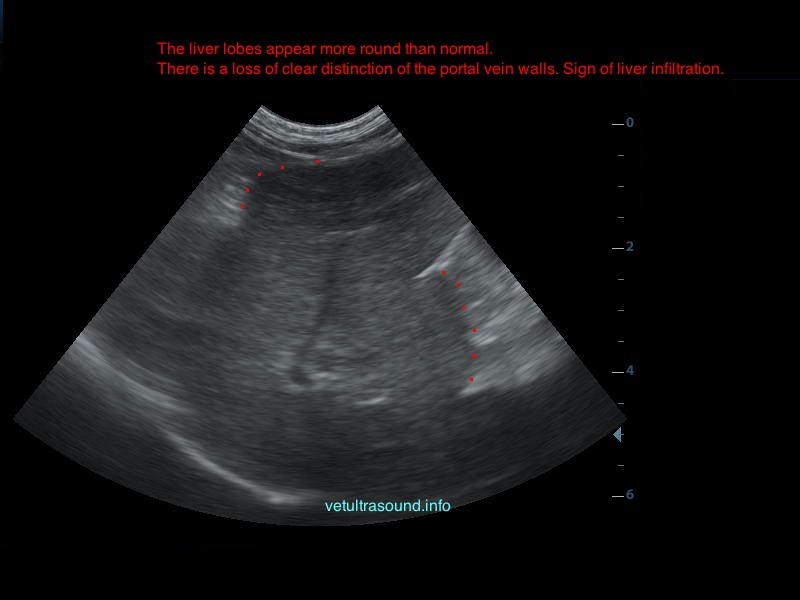

Ήπια ηπατομεγαλία με αύξηση της ηχογένειας του οργάνου, χωρίς παρουσία εστιακών αλλοιώσεων(pic.4). Πάχυνση του τοιχώματος της χοληδόχου κύστης με εικόνα βλεννοκήλης ( kiwi sign) και έντονη υπερηχογένεια στη περιοχή περί αυτού(pic.1&2). Ήπια διάταση της νεφρικής πυέλου, πιθανόν λόγω της πολυουρίας και πολυδιψίας(pic.3). Επασβέστωση στον οπίσθιο πόλο του δεξιού επινεφριδίου και αύξηση των διαστάσεών του(pic.6). Απουσία ασκιτικής συλλογής και παθολογικά διογκωμένων λεμφαδένων.